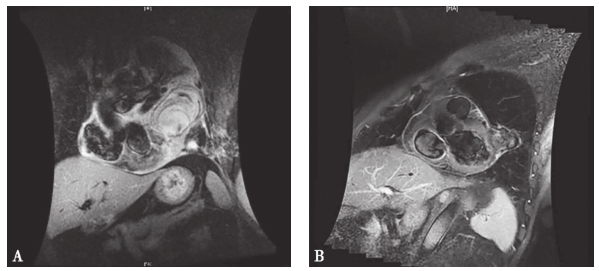

心脏磁共振(2013年2月18日)(图1A):心包内占位,回旋支假性动脉瘤可能,合并心包积液,左侧胸腔积液;结合CT左舌段下肺动脉纤细,动脉炎相关?左下肺膨胀不全并肺间质改变。

图1 心脏磁共振

A:2013年2月心脏MRI示冠脉回旋支动脉瘤大小9.5cm × 6.5cm;B:2014年12月心脏MRI示冠脉回旋支动脉瘤大小3.8cm × 2.7cm

随访14个月患者病情稳定,无反复,冠状动脉瘤明显缩小(见1B)。